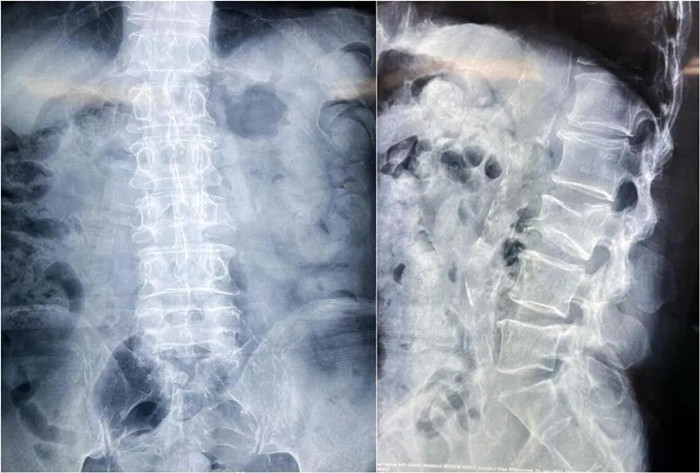

患者情況:腰椎L3壓縮性骨折

南京醫(yī)科大學(xué)第二附屬醫(yī)院骨科副主任醫(yī)師王伯堯帶領(lǐng)團隊成功完成經(jīng)皮椎體球囊擴張成形術(shù)(PKP)。該患者為腰椎陳舊性壓縮性骨折,腰部疼痛難忍,活動受限,生活受到影響。王醫(yī)生借助普愛醫(yī)療大平板C臂機高清的圖像及靈活的擺位,快速定位椎弓根位置,確定進針點,使得手術(shù)得以更加高效和準(zhǔn)確地完成。

患者術(shù)前影像